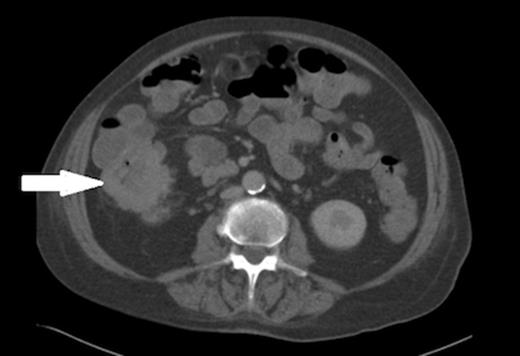

Urine microscopy was normal but blood cultures taken on the day of admission grew Escherichia coli (E. coli) and this, coupled with iron deficiency anaemia prompted a search for other pathology and a CT scan of chest, abdomen and pelvis showed thickening of the ascending colon (figures 2 and 3). A colonoscopy confirmed a fungating lesion in the mid-ascending colon and biopsies showed adenocarcinoma of the colon. Our patient then had a laparoscopic right hemicolectomy followed by adjuvant chemotherapy for a moderately differentiated adenocarcinoma (pT4 N2 V1 R0 M0). Her discitis settled with antibiotic treatment.

Axial view of the CT abdomen showing thickening of the ascending colon (indicated by arrow).